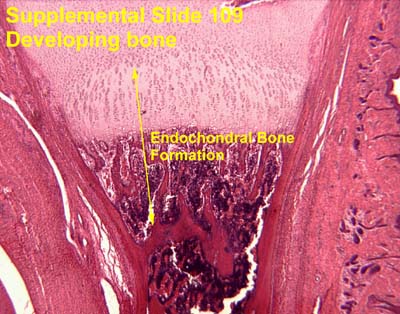

Supplemental Slide 109 Developing bone.

Another example of endochondral bone formation.